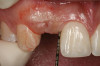

Figure 21   Gingival zenith planning: The location of the gingival zenith for this missing lateral incisor is not fully evident during initial clinical evaluation (Fig 21). Subsequent diagnostic waxing reveals the position of the planned gingival zenith (Fig 22). A thermoplastic template captures the position of the zenith and enables transferring this location to the clinical environment (Fig 23 and Fig 24). Final crown contours are defined by soft-tissue form (Fig 25).

Figure 22  Gingival zenith planning: The location of the gingival zenith for this missing lateral incisor is not fully evident during initial clinical evaluation (Fig 21). Subsequent diagnostic waxing reveals the position of the planned gingival zenith (Fig 22). A thermoplastic template captures the position of the zenith and enables transferring this location to the clinical environment (Fig 23 and Fig 24). Final crown contours are defined by soft-tissue form (Fig 25).